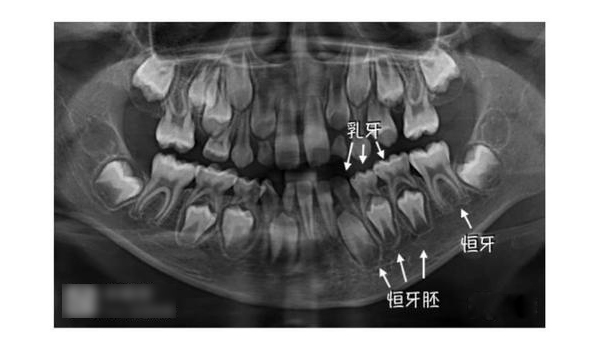

家長不必過分擔(dān)心寶寶牙齒出得慢。一般要到三歲左右,寶寶的乳牙才會完全出齊。與此同時,恒牙大部分也正在孕育之中。當(dāng)寶寶步入小學(xué)時,會長出第一顆六齡齒。一般等到小學(xué)高年級后,乳牙會全部脫落,換上滿口的恒牙。但也有的孩子到了中學(xué)才換好牙齒。

這是一個誤區(qū)。健康的乳牙可以保證恒牙的正常發(fā)育和引導(dǎo)恒牙正常萌出。乳牙如發(fā)育不正?;蚧箭x齒的話,會直接影響到恒牙的發(fā)育,如乳牙齲齒特別嚴(yán)重的話,會影響到乳牙牙根根尖部位,甚至下方恒牙的牙胚。因此父母不能掉以輕心,一旦發(fā)現(xiàn)齲齒要及時請醫(yī)生治療、填補。